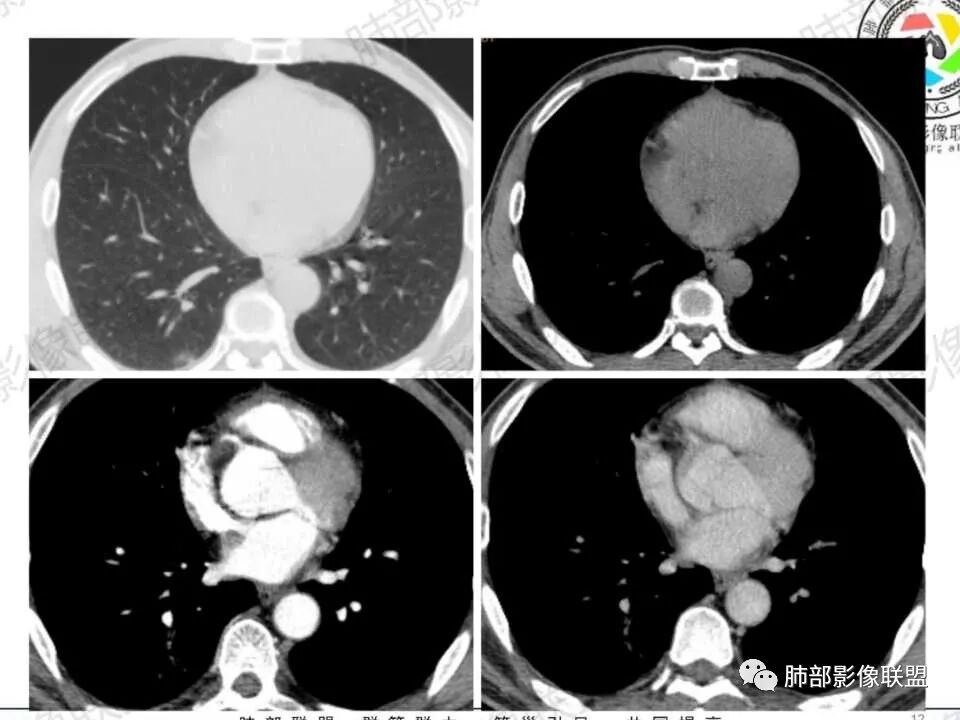

1.中年男性,发现肺部结节增大就医(一年前发现肺部结节),缺乏临床表现。有糖尿病基础。

2.右肺下叶背段指尖大小结节影伴外围片状影及小结节影,片影中有结节感。

3.近背段支气管开口附近结节密度不甚均匀,未见钙化或脂质密度区。边界清楚光整,内侧平直,未见典型深分叶及毛刺,增强扫描轻度强化。

4.哌拉西林、左氧氟沙星等治疗一周后,较大结节影及外围病灶范围均见增大。

5.背段支气管于结节内侧份“旁现侧出”,管壁完整,管腔少量分泌物,近乎疏通状态。结节内隐约出现微小含气空腔。

6.肺门及纵隔未见增大淋巴结。

1.会是肺腺癌吗?较长时间段内固定存在的结节影我们会想到新生物。本例结节影边界清楚光整,内缘平直,缺乏典型深分叶及毛刺,未见异常强化,未见肿大淋巴结等,缺乏肺腺癌的依据。

2.会是硬化性肺细胞瘤吗?病灶支气管相关,未见异常强化,短期内增大等几乎完全将硬化性肺细胞瘤排除在外。

3.同样的理由也不支持错构瘤,尽管结节影密度不均匀。我们几乎不可能在错构瘤中观察到如此穿行的支气管!

4.会是隐球菌感染吗?急性感染,如易形成空洞的肺炎克雷伯杆菌感染等我们自然不在考虑之列,无论是临床表现还是影像学改变。肺部隐球菌病灶有时酷似新生物,但如此漫长不出新花样的侵袭性病灶则非常罕见!

5.临床表现轻微的病灶还有肺结核!可以长期“默默无闻”。本例结节影密度欠均匀,强化不显著,可以出现小空洞,周围见小结节影等,结核确实存在众多支持点。

不事张扬的小空洞,最常见的还是结核!

6.外围片影的迅速扩大应考虑为继发性改变,不宜单以结核感染本身加以解释。